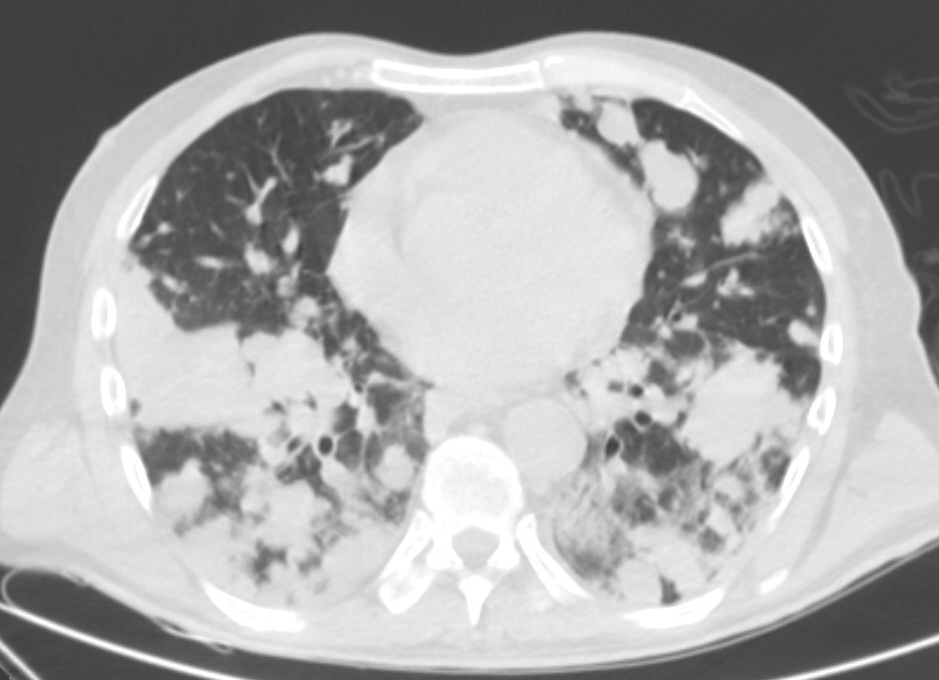

4: Miliary pattern: sarcoidosis, CT, lung window. Axial image and sagittal reformat.

A 67 year old female suffering from COPD. Bilateral rough branching interstitial widening and patchy, miliary nodules with perihilar dominance along the bronchovascular fibres and the fissures.